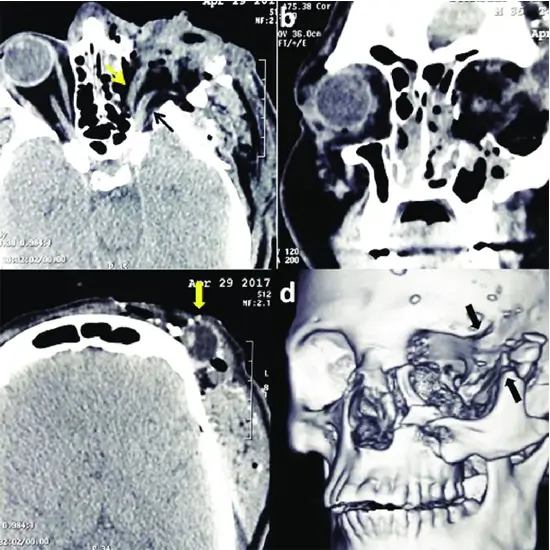

NCCT Face Coronal is non-contrast computed tomography of the face at the coronal plain. This scan evaluates the facial bones, orbits, sinuses, mandible (jaw), and maxilla. This scan is useful in detecting fractures of facial bone and other disorders/diseases affecting the facial bone and its surrounding tissues.

Doctors usually recommend this scan to detect the problems/ diseases affecting the facial bone and nearby tissues. It is used to diagnose/ detect facial bone injury, mass lesions, maxilla bone injury, mandible injury, orbit injury, sinus infections, eye infections, and tumors of the face and nearby tissues.